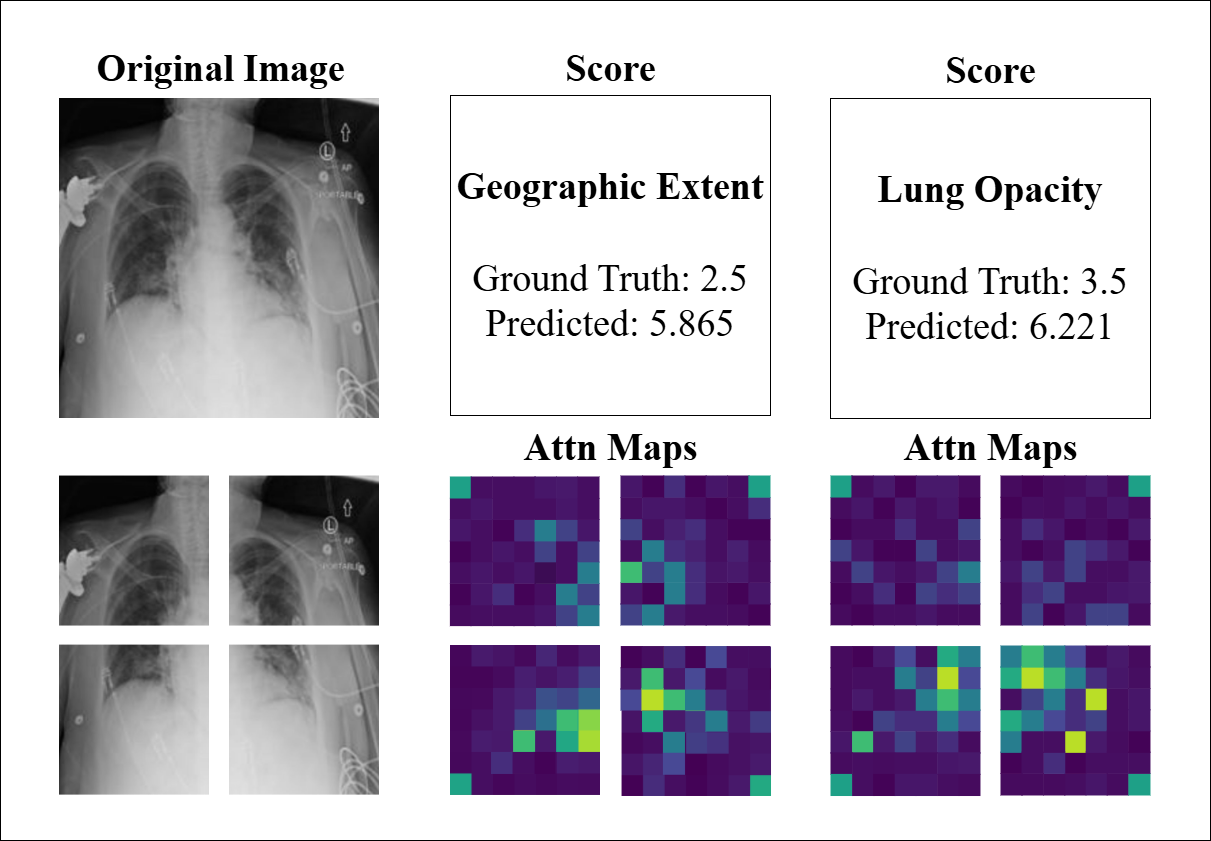

4.4 Model Interpretability

To further evaluate the interpretability and consistency of our model, we conducted a visual inspection of attention maps and prediction outcomes across representative CXR and CT cases. Figure 7 displays three CXR examples alongside their corresponding quadrant-wise attention maps that represent the output of the four PVT encoders, as well as the GT and predicted scores for both GE and LO. The attention maps demonstrate the model’s ability to localize clinically relevant radiographic features, with predictions largely consistent with GT scores (e.g., LO: GT 3.0 vs. predicted 2.714). Notably, the attention weights align with the predicted severity, as the model’s scores reflect the proportion of high-weight regions within the maps. However, the last example (GT 2.5 vs. predicted 5.86) exhibits a significant deviation. While the attention maps highlight diffuse areas of activation, the overestimation may arise from image-quality limitations, such as low contrast or anatomical noise, which could lead the model to misinterpret benign variations as pathological findings. This underscores the influence of technical artifacts on model performance and highlights the need for robust preprocessing to enhance reliability.